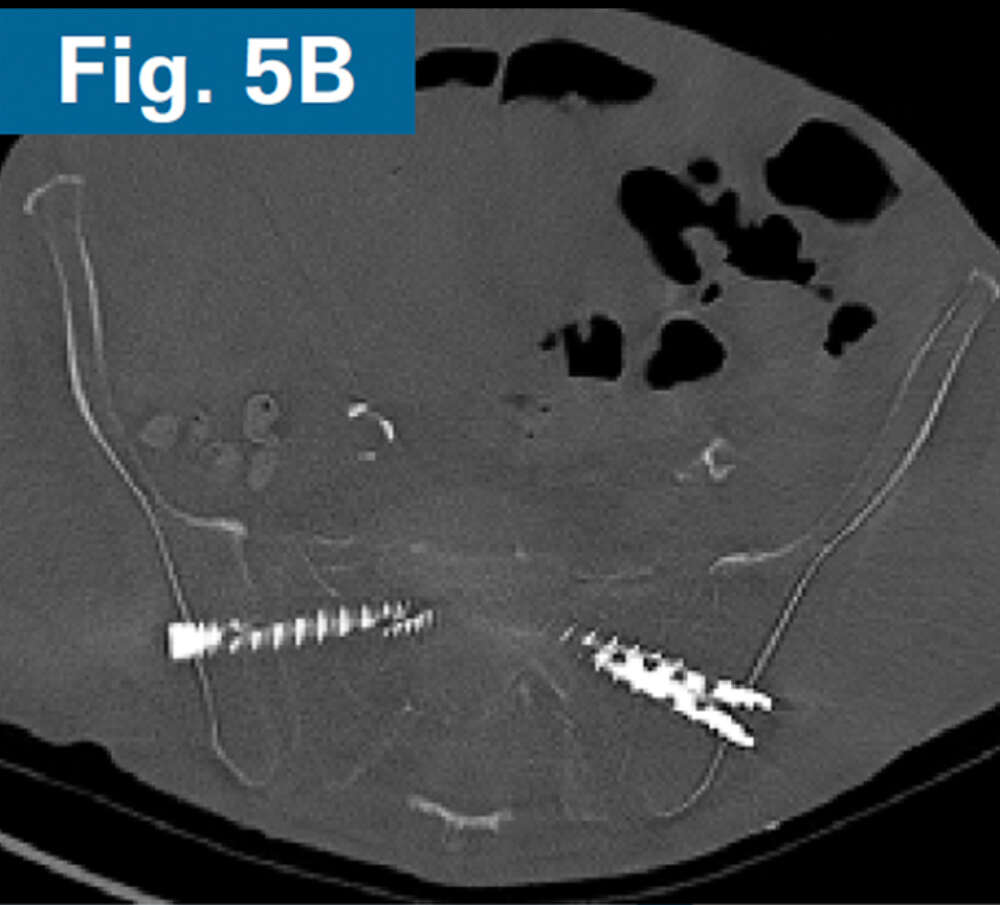

• Immediate postoperative CT scan demonstrate safe placement of implants (Figs. 5A and 5B).